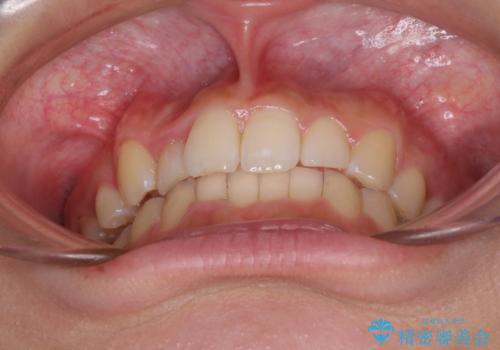

- 上顎の重なっている前歯を気にして来院された患者様です。

八重歯改善には抜歯が必要で、八重歯の移動量が多く、更には右側にずれている正中を改善する必要がありました。

インビザライン単体での治療は困難と判断し、補助装置により八重歯移動後にインビザラインを用いることとしました。

インビザラインでは治療期間が延びることが予想されたため、ワイヤー矯正を提案しましたが、セラミッククラウンが多く、壊すあるいは傷が付く可能性があることから、長期間であってもインビザラインを選択されました。